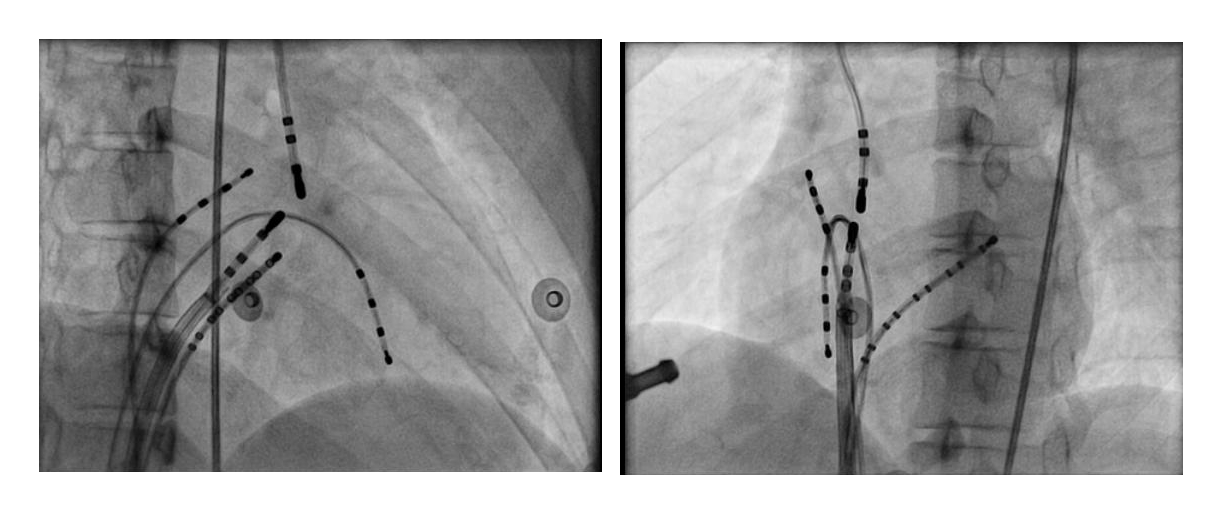

#5 Mapping in diverticulum - CSE potential most important

#6 Oblique pathways - Earliest A / V may be distant

med_lat.jpg

#6 Oblique pathways - AP potential more important than earliest A

pot_late_a.jpg